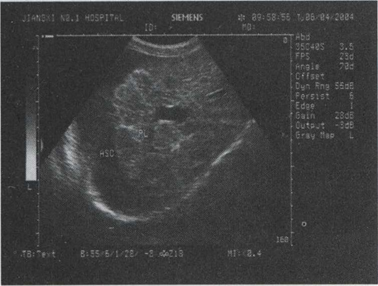

35.男,70岁,血吸虫疫区接触史,上腹胀痛,腹膨隆。脾大,门静脉增宽。结合超声声像图,诊断为()